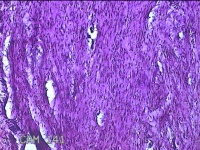

前胸部包块

性别

女

年龄

45岁

临床诊断

皮脂腺囊肿

一般病史

发现前胸部包块3个月余。

标本名称

大体所见

灰白暗红色组织2.2x1x0.8cm一块,表面带梭形皮肤2.2x1.3cm,皮下见包块1.8x1.2x0.8一块,切开包块呈实性,切面灰白粉红色,质软。